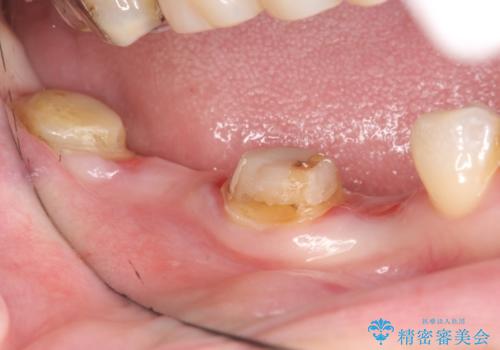

- 右下の奥歯の被せ物が外れてしまったので診て欲しいといらっしゃった方の症例です。

右下7は欠損しており、右下5は保存不可能だったため、インプラントによる欠損補綴を行いました。